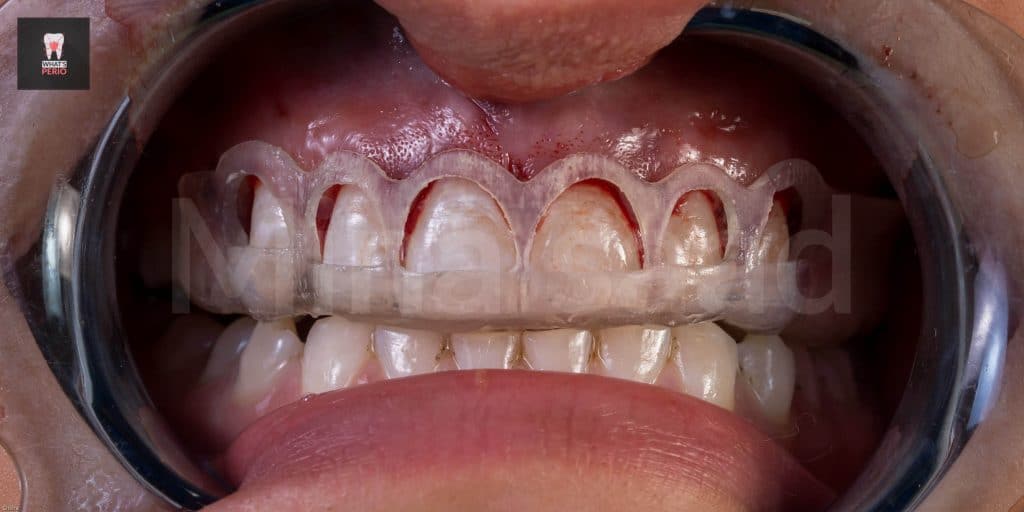

-The guide was printed & was tried over a 3d model & also intraorally to check the coronal level is exactly like the pobing depths which were taken.

-External bevel gingivectomy was made while the guide in place.